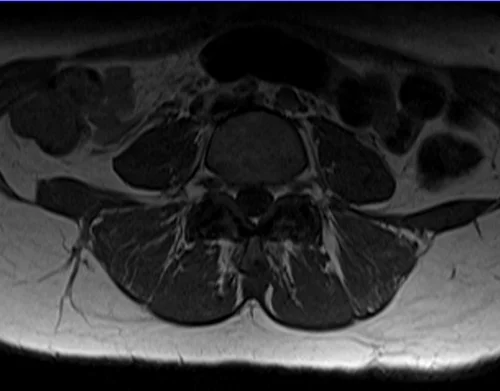

L plexus mri T1 axial images